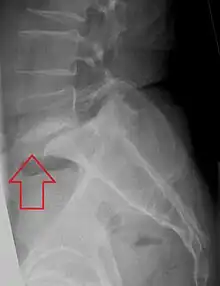

Espondilolistese na vértebra lombar L5.